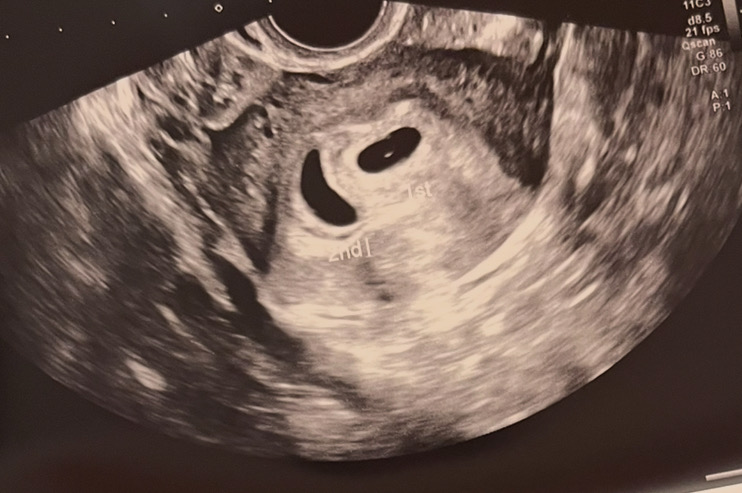

쌍둥이 아기집인데 한명은 아직 난황이 안보여요

5주 4일차에 초음파 보고왔어요! 쌍둥이인데 한명은 이쁘게 난황까지 보여주엇고 한명은 아직이네요ㅠㅠ 이왕 아기집까지 만들었는데 두명 다 만나고싶어요. 아직 난황 안생긴 둘째도 곧 난황 만들겠죠. 부모님한테는 둘째까지 난황 만들고나서 임밍아웃 하고싶은데ㅠㅠ 다음주에 초음파 볼때 생기려나 걱정이네요ㅜㅠ